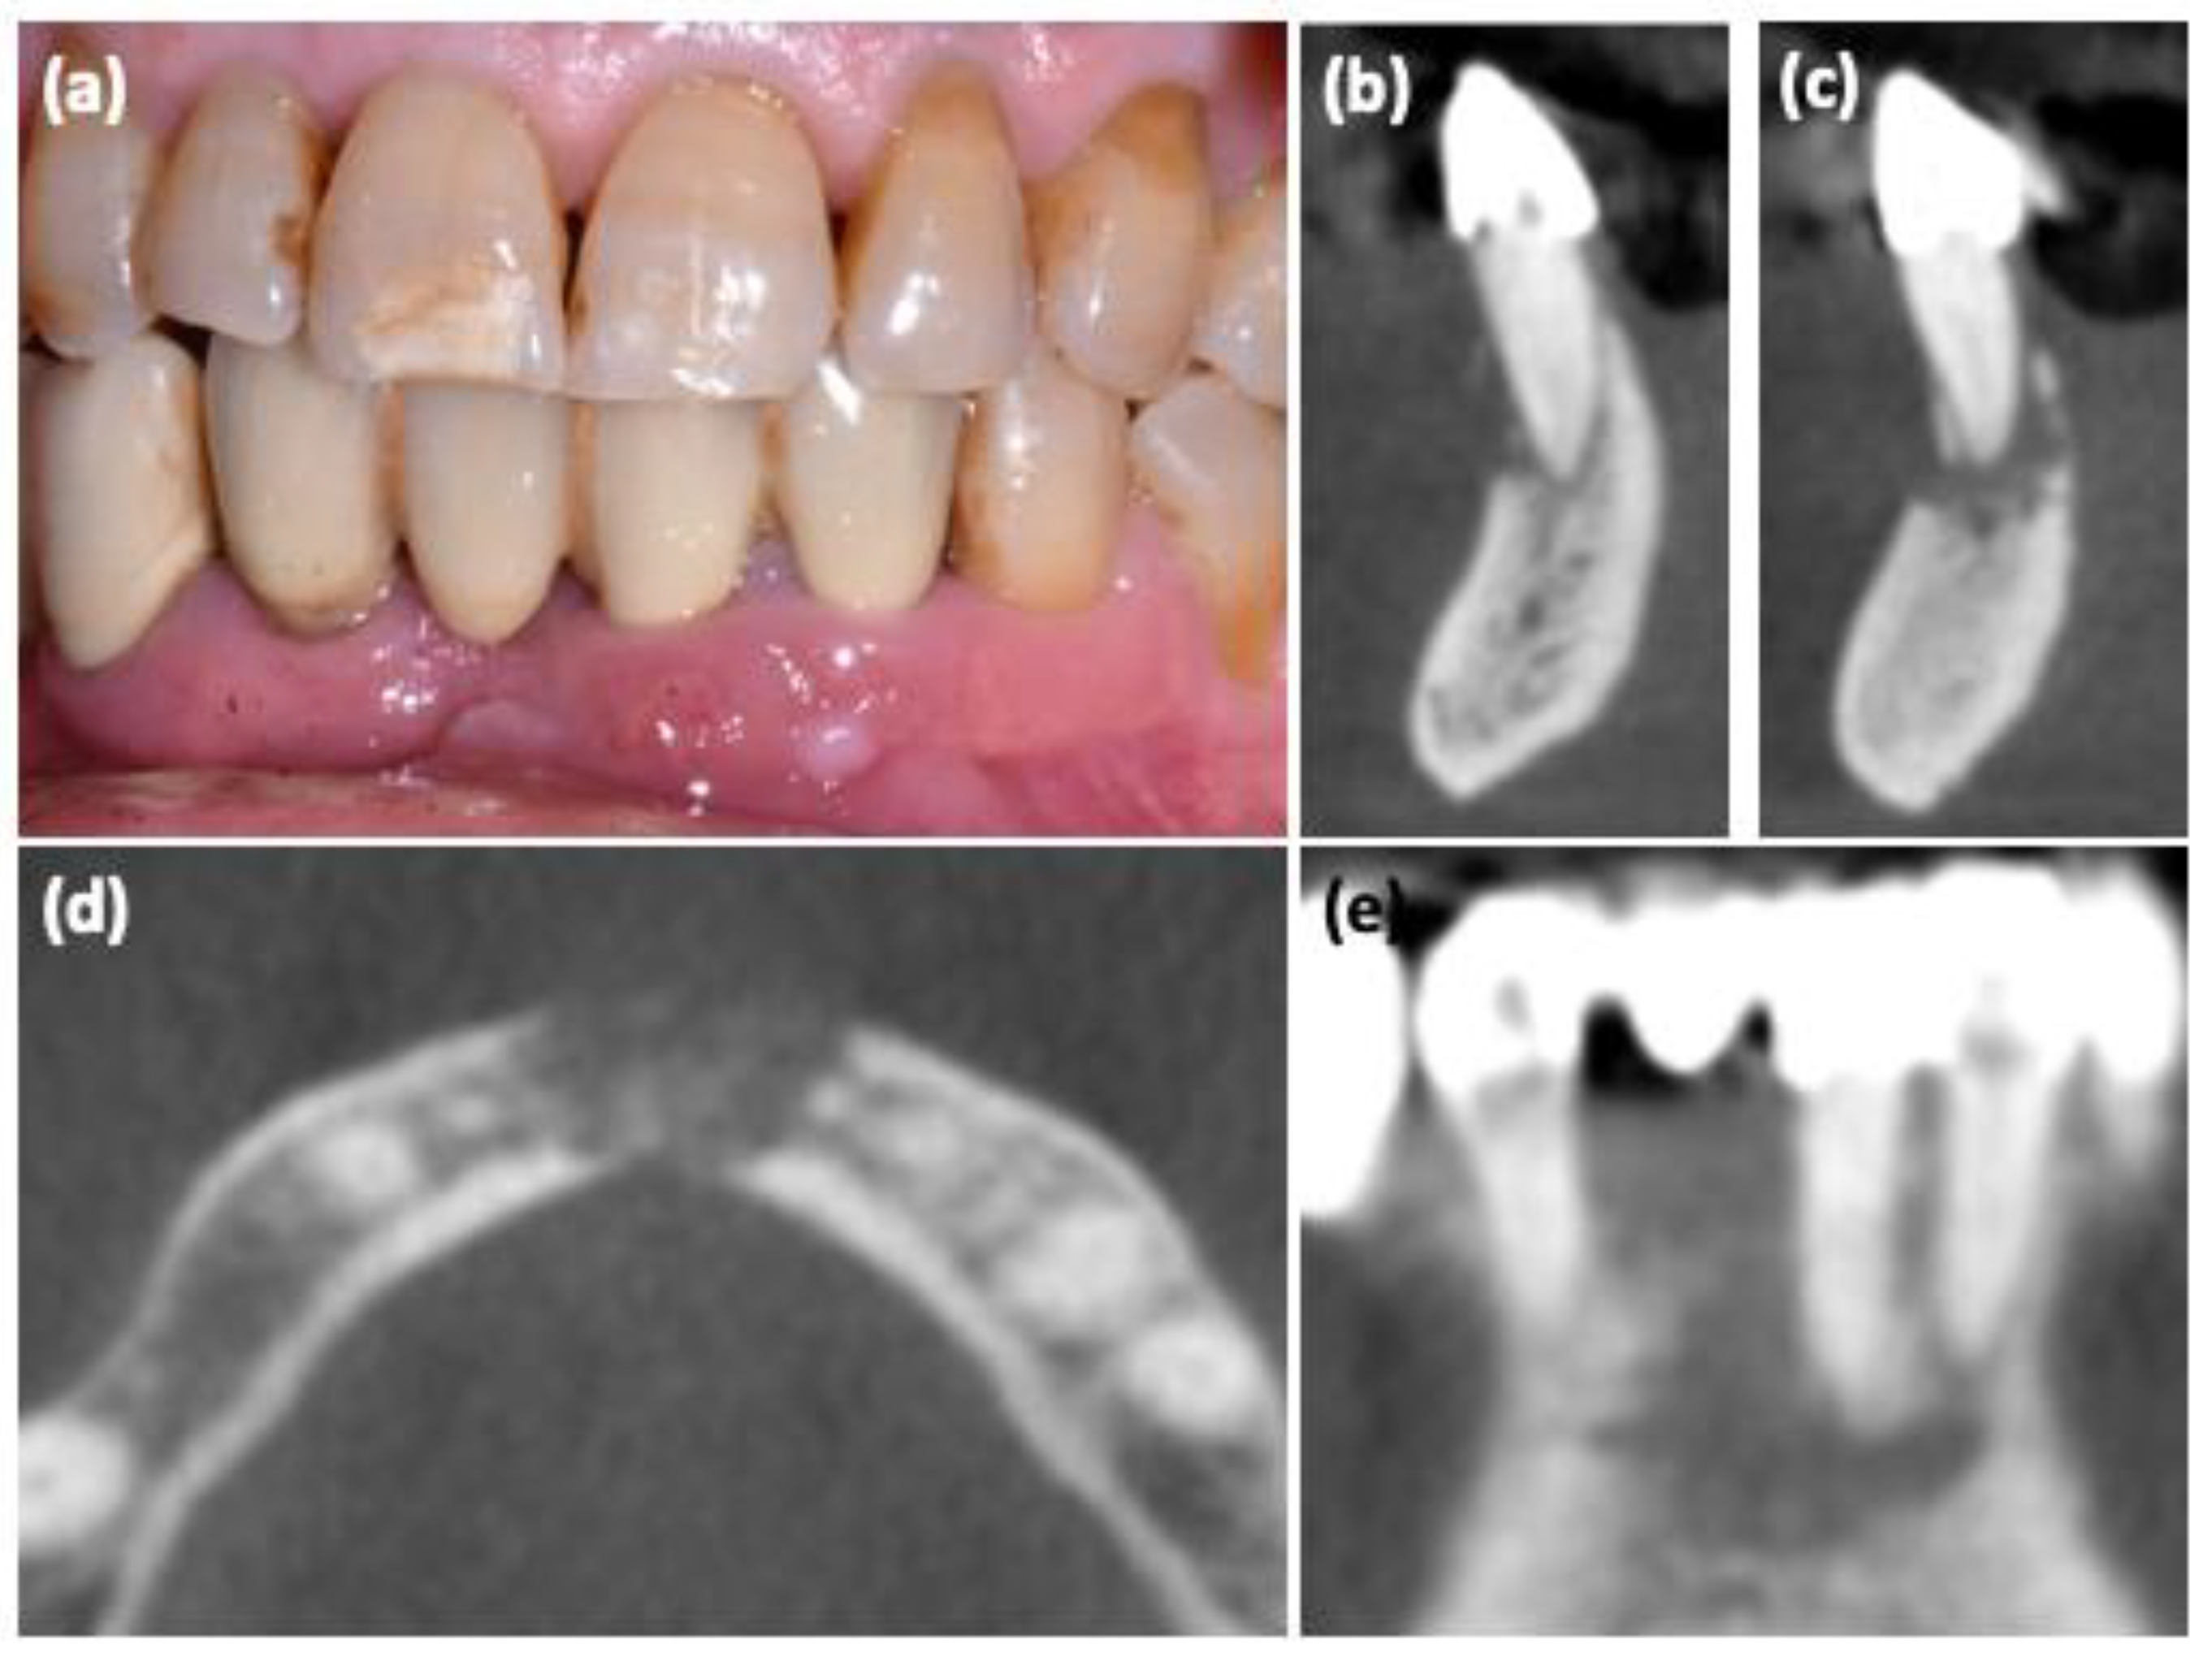

| #1 | 75 | F | Yes | Yes | risedronate Xgeva® | 48 60 | 7200 7200 | Anterior lower jaw | I | Intraoral Fistula, Tooth mobility | |

| #2 | 56 | F | Yes | Yes | Prolia® zoledronate | 20 16 | 180 64 | Posterior upper jaw | I | Tooth mobility | |